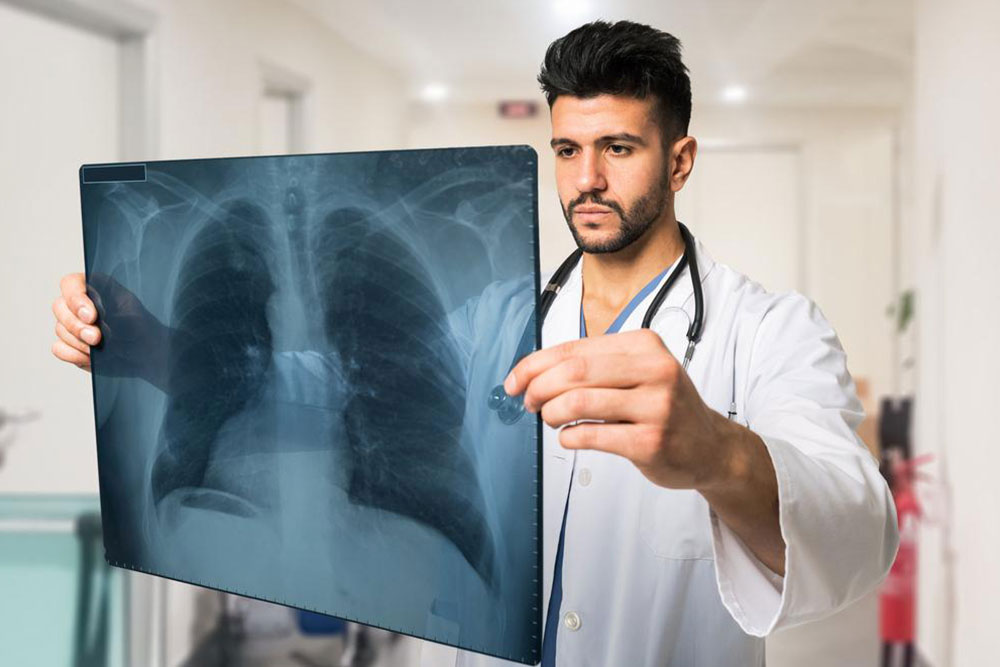

Pneumonia symptoms – Things one should know about

Pneumonia is a bacterial infection that is spread by the bacteria known by the same name. This condition is caused due to exposure to cold temperatures when the person is suffering from even slight flu and cold. This condition can also get worse and more complicated if the patient is already suffering from additional diseases like diabetes and heart disease.